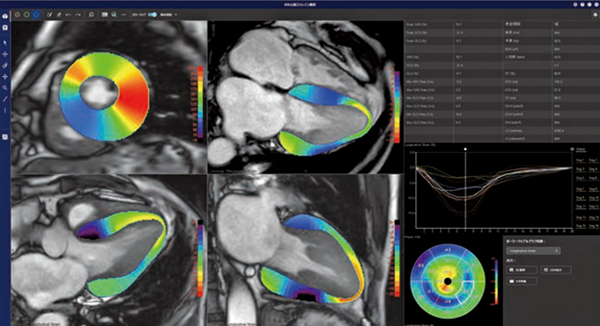

MRIによる心筋ストレイン評価は,心筋運動による壁厚の変化を定量的に評価する方法であり,日本循環器学会の「2020年版 心アミロイドーシス診療ガイドライン」ではクラスⅡaとして推奨されている。REVORASの「MR心筋ストレイン解析」では,MRIのデータを開いた後,短軸像および長軸像(2ch,3ch,4ch)のすべての断面において,左室心筋内壁と外壁の輪郭線が自動で抽出される。手動で輪郭線の修正を行った場合も,各スライスやフェーズにおいて輪郭線が自動で補間されるため,効率的に解析作業を行うことができる。円周方向(circumferential strain),心筋の中心部方向(radial strain),左室長軸方向(longitudinal strain)の3方向での評価に加え,各セグメントのストレイン評価やポーラーマップでの解析結果の表示も可能である(図3)。

図3 MR心筋ストレイン解析